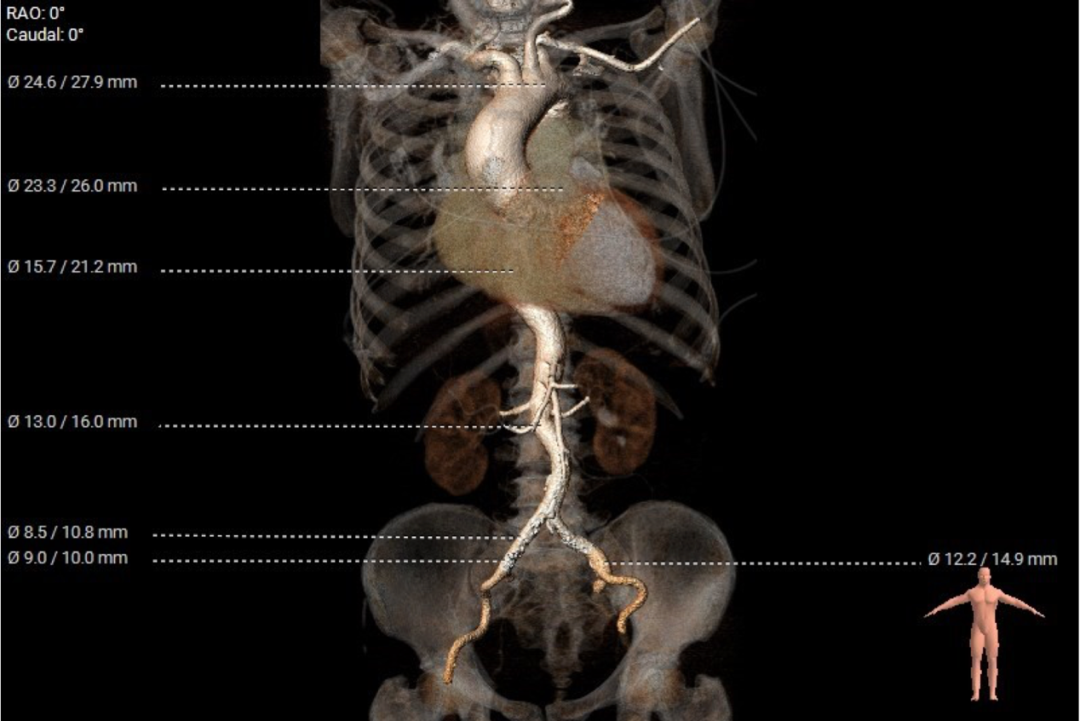

升主动脉增宽,最大径44.6mm:

重度钙化,850HU下765mm³:

主动脉弓、降主动脉及双侧髂总动脉散在钙化,降主动脉走行迂曲,胸-腹主动脉成角84°:

左髂总动脉局部增宽: